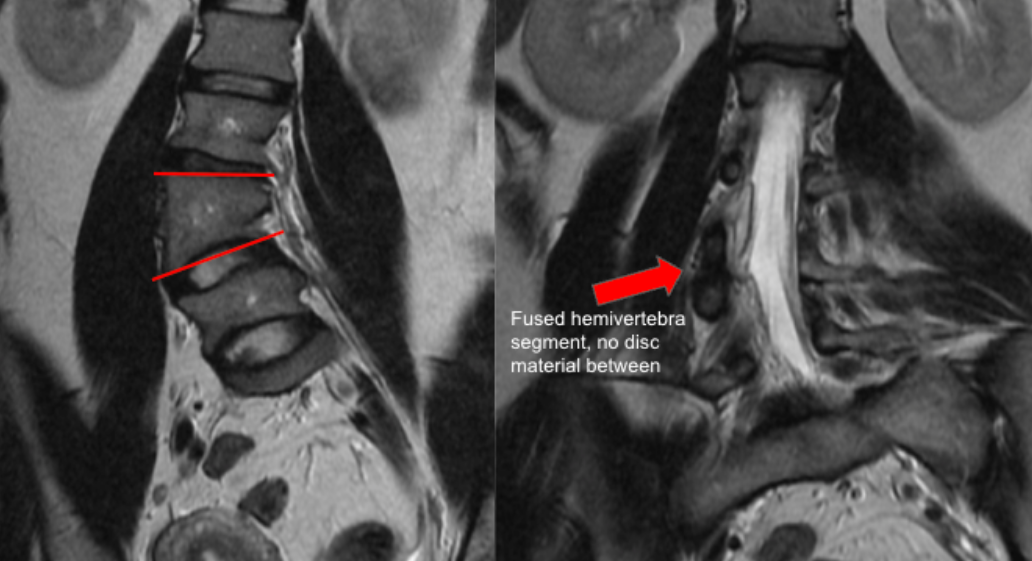

A. Wedge Angle Measurement (Coronal MRI)

• Select a coronal MRI slice that best visualizes the hemivertebra and adjacent vertebrae.

• Identify the superior and inferior endplates of the hemivertebra.

• Draw a line along the superior endplate of the hemivertebra.

• Draw a second line along the inferior endplate of the hemivertebra.

• Measure the acute angle between these two lines — this is the hemivertebral wedge angle (degrees).

B. Segmentation Assessment (Axial + Coronal MRI)

•  Evaluate the intervertebral discs above and below the hemivertebra.

• Classify segmentation as:

• Fully segmented: Disc spaces present both above and below

• Semi-segmented: Disc present on only one side

• Unsegmented (incarcerated): No disc spaces above or below, fused to adjacent vertebrae